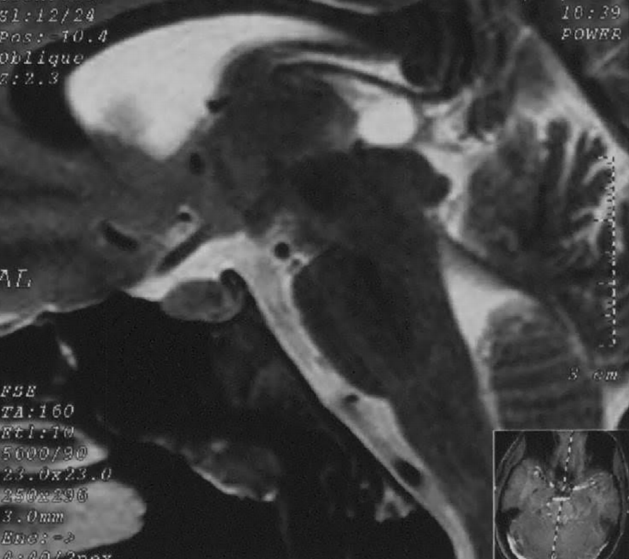

18歲男性松果體囊腫伴上丘壓迫- MRI矢狀T2圖像。